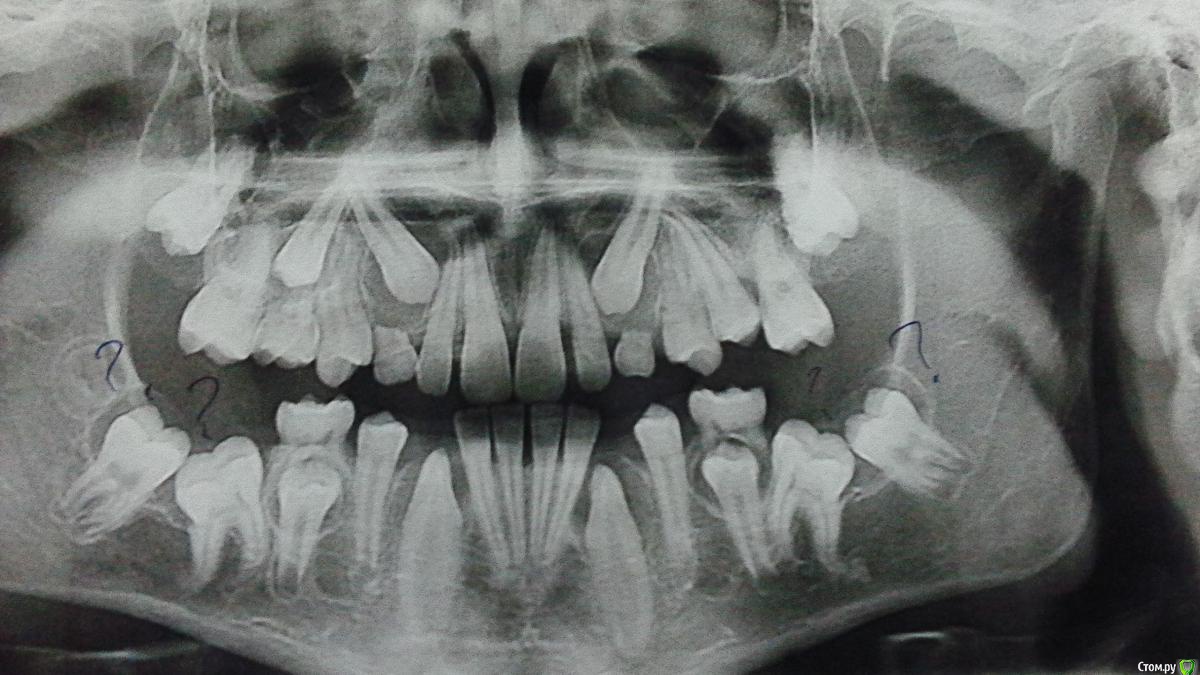

Лели Опубликовано 4 ноября, 2015 Поделиться Опубликовано 4 ноября, 2015 Ув. доктора эта тема открыта в ортодонтии. Мальчик 14 лет с вот такой ретенцией. Какой прогноз с Вашей точки зрения. Ссылка на комментарий